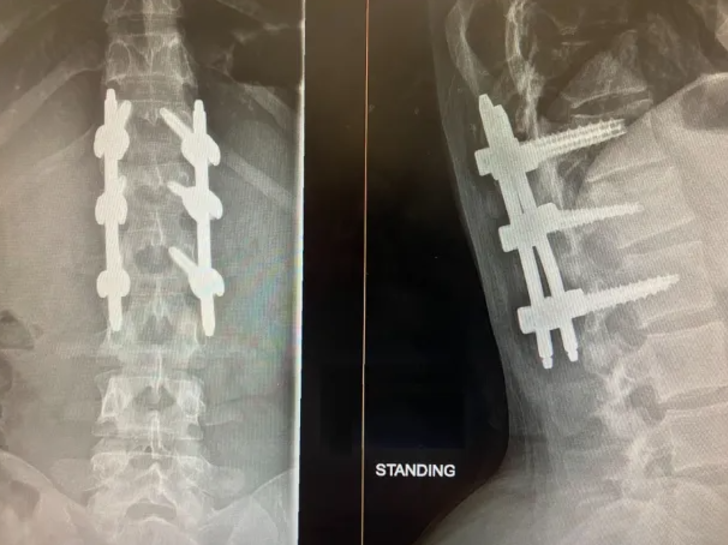

Atlayışının sonrasında acı içinde bağıran Sinden’in yardımına İtfaiye, ambulans ve dağ kurtarma ekipleri koştu. Hastaneye kaldırılan Sinden’in omurgasından altı saatlik bir operasyon yapıldı ve omurgasındaki kemikler metal çubuk ile titanyum vidalarla birleştirildi. Dört ay boyunca tekerlekli sandalyeye bağımlı yaşamak zorunda kalan Sinden, yürümeyi adeta yeniden öğrendi.